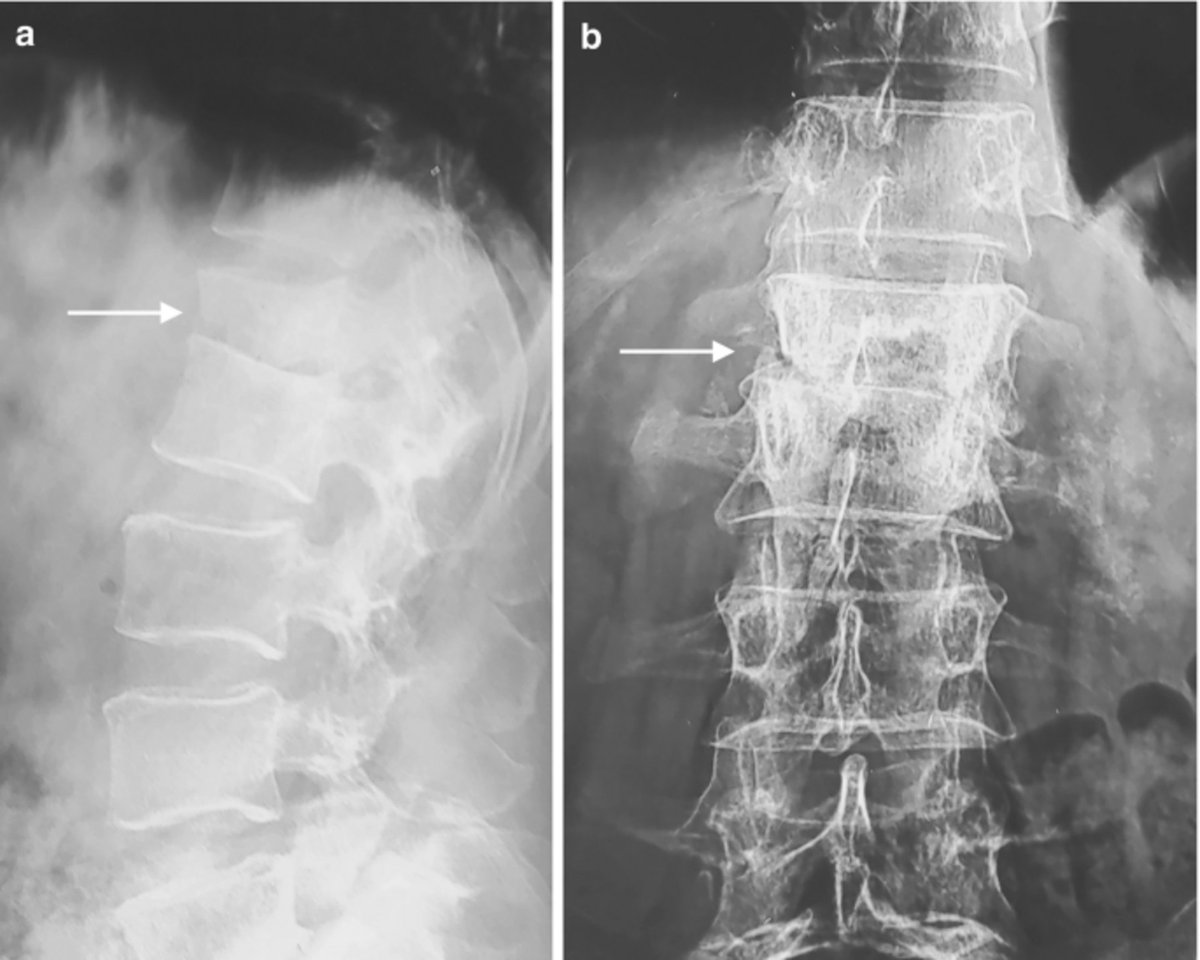

This spinal X-ray appearance is classic for? A. Tuberculosis (Pott's spine) B. Rheumatoid arthritis C. Ankylosing spondylitis D. Osteoporosis #NEETPG #MedTwitter Dr. Akhil 🇮🇳 Antonio Arroyo, MD. Medico Cirujano. Dr. Priyam Bordoloi Dr. Shiv_Kumar Dr. Medica🩺 SAGE MEDICAL⚕️